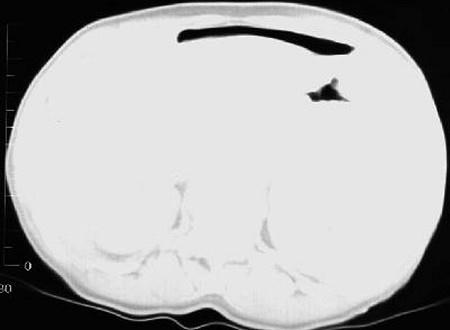

问题 男,44岁,突然中上腹痛,压痛,反跳痛,腹肌紧张,发热,白细胞计数升高,CT检查如图,最可能诊断是 ( )

选项 A、胰腺癌 B、胃癌 C、慢性胰腺炎 D、胃小弯溃疡穿孔 E、急性胰腺炎

答案 D